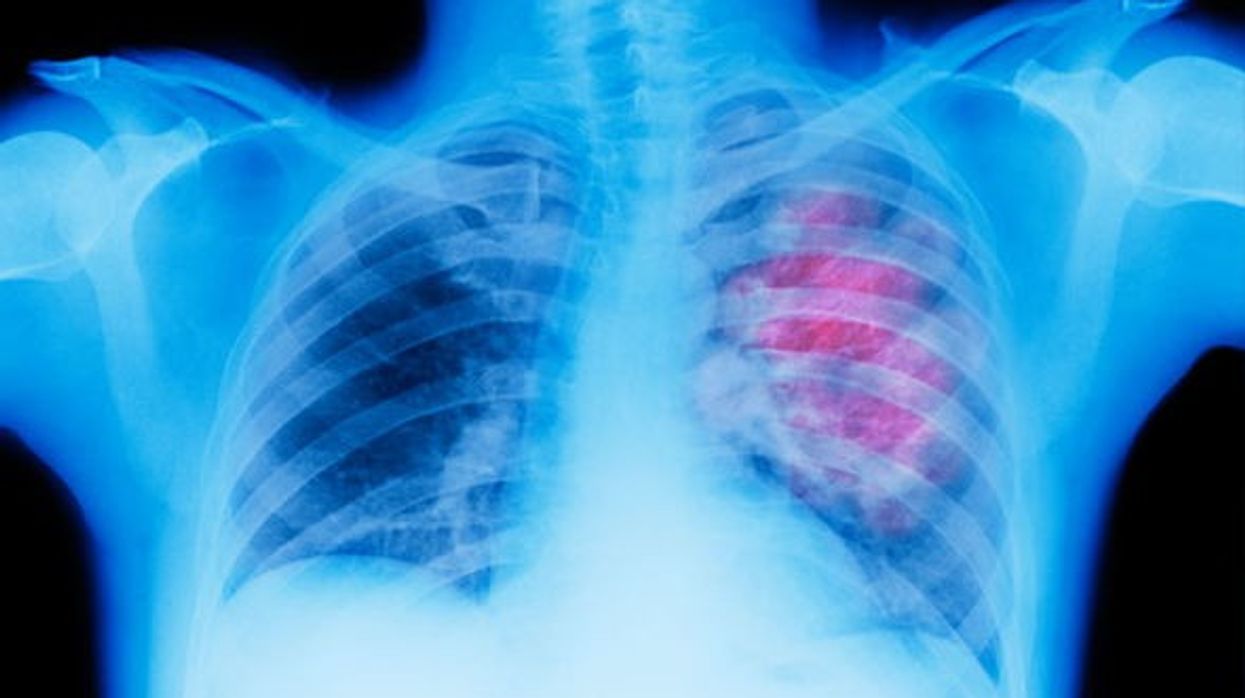

Rrezatimet ultraviolete në gjoks janë hapi kryesor, por nuk janë të mjaftueshme. Skanimet e CT-së janë të rëndësishme për të parë më mirë gjendjen e shëndetit tuaj.

Veç kësaj, CT është mënyra më e mirë për të njohur shkallët e para të sëmundje në gjoks, duke përfshirë edhe simptomat e kancerit në mushkri.